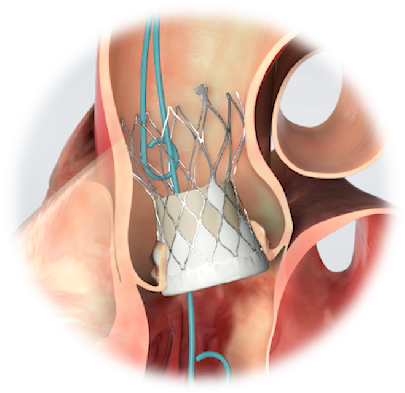

考虑到实施常规开胸体外循环手术难度高、风险大,依老唐目前的状况,是不可能完成的。心脏大血管外科主任潘禹辰带领团队联合心血管内科、麻醉科、手术室、介入室、肾内科、营养科、康复科等进行了多学科会诊,并将手术风险充分告知患者家属,在结合患者实际病情综合评估、征得家属充分理解之后,救治团队决定采用“微创不开胸换瓣手术”,即经导管主动脉瓣置换术(TAVR)。

对严重主动脉瓣病变患者,常规外科体外循环直视下主动脉瓣置换术(SAVR)曾经是唯一可以延长生命的治疗手段,但老年患者常因高龄、体质弱、病变重或合并其它疾病而不能手术。对于存在高危或有外科手术禁忌的患者,现在,经导管主动脉瓣置换术(TAVR)则可以作为一种有效的治疗手段,具有创伤小、恢复快、风险低等优点。既往做TAVR手术的绝大多数患者都是主动脉瓣严重钙化狭窄,因为有钙化的锚定区易于瓣膜固定,而主动脉瓣返流的患者,瓣环及瓣上结构一般都较大,锚定区少,因此,单纯主动脉瓣严重返流的患者实施TAVR手术难度非常大,某些患者因缺乏锚定区而无法实施微创手术。

家属性命相托,医生全力以赴。在充分的术前准备下,潘禹辰主任团队在短时间内顺利为老唐进行了微创经导管主动脉瓣置换手术(TAVR),给患者置换了一个新的“心门”。手术过程惊心动魄,大瓣环纯返流,窦部及升主动脉扩张,术中难以锚定瓣膜,先后经历更换导丝、更换瓣膜、五次释放才将人工瓣膜精准释放到位。